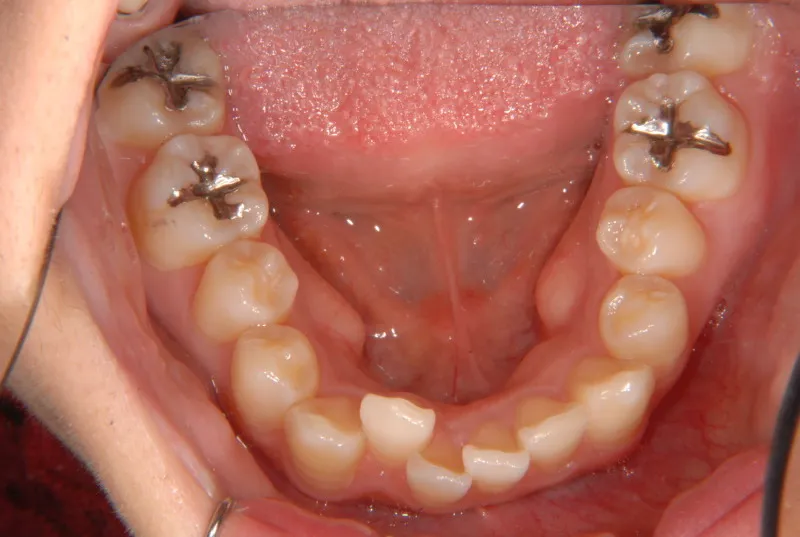

初診時年齢 19~29歳 (女性) 主訴 ガタガタ・90度ねじれている

診断名 叢生・上顎前突 装置名

奥歯が内側と前方にかたむき上下の歯がガタガタに生えています。

90度ねじれた歯もあります。前歯も出っ歯になっています。

歯は抜かず、歯科矯正用アンカースクリューを用いて治療しました。